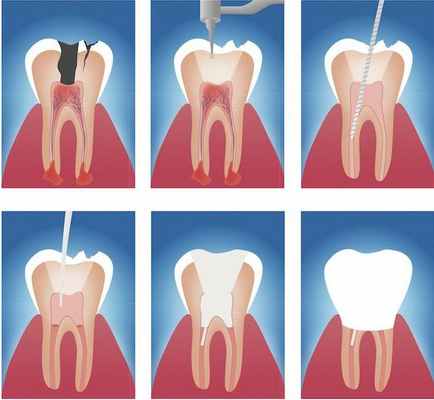

Лечение периодонтита в нашей клинике включает в себя:

- Постановка анестезии;

- Препарирование зуба (снятие пломбы);

- Наложение коффердама;

- распломбировка каналов (ранее леченых каналов)

- Механическая и медикаментозная обработка канала;

- Временное пломбирование;

- Пломбирование корневого канала (1-4 канала);

- Наложение временной пломбы;

- Наложение изолирующей прокладки;

- Наложение пломбы;

- Применение набора антиСПИД

- Рентгеновский снимок.

Этапы эндодонтического лечения:

- адекватное обезболивание;

- изоляция зуба или нескольких зубов, в которых будут проводится манипуляции, от полости рта;

- создание эндодонтического доступа (иссечение твёрдых тканей зуба или пломбировочного материала, закрывающих доступ в систему корневого канала;

- прохождение и определение длинны корневого канала (это длинна от устья до верхушки корня);

- создание корневого канала определённого диаметра и формы;

- введение в корневой канал лекарственных препаратов;

- пломбирование корневого канала;

- восстановление анатомии и функции зуба с помощью пломбировочного материала или ортопедической конструкции.